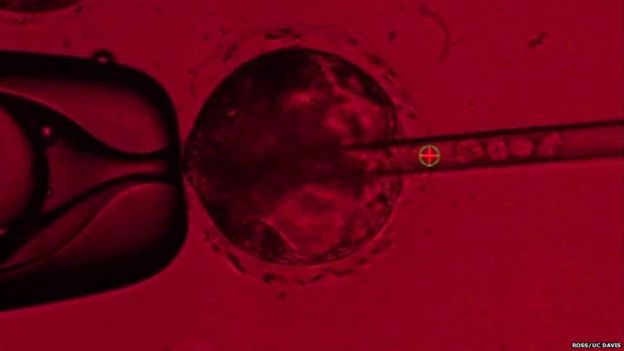

ФОТО: Человеческие стволовые клетки вводят в эмбрион свиньи.

С помощью технологии CRISPR (Clustered Regularly Interspaced Short Palindromic Repeats) ученые удаляют у эмбрионов свиней фрагмент ДНК, ответственный за создание поджелудочной железы и вводят в эмбрионы индуцированные стволовые клетки человека, сообщает британская BBC.

В результате ученые надеются, что из этих клеток разовьется полноценная человеческая поджелудочная железа.